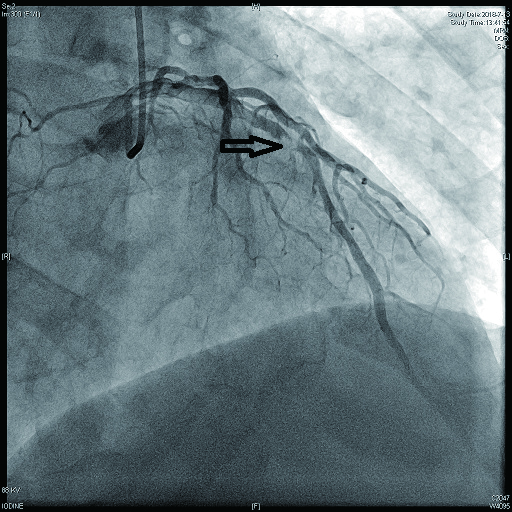

病例4 3 LAD中段及D1(图 11 LAD 85%及D1闭塞 0级 LAD中段植入支架1枚

图 11 病例4冠脉造影示LAD狭窄,D1闭塞